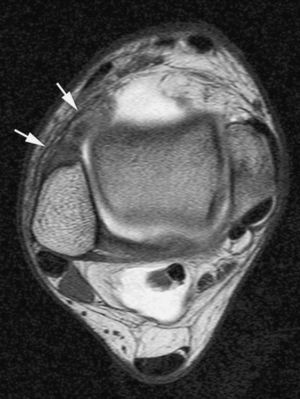

Las plicas sinoviales son remanentes embriológicos del tejido sinovial normalmente asintomáticos. La inflamación crónica de las plicas sinoviales causada por un traumatismo o microtraumatismos repetidos produce una disminución de su elasticidad. Las plicas patológicas o sintomáticas aparecen engrosadas, fibrosas y rígidas. Con la movilización de la articulación producen irritación de la sinovial y erosiones del cartílago13,24.

La plica más frecuentemente sintomática es la mediopatelar. El dolor se produce por el roce de una plica rígida con el cóndilo femoral medial que conduce a sinovitis mecánica, erosión del cartílago articular del cóndilo femoral medial y de la faceta rotuliana interna. El dolor generalmente es intermitente, se acentúa con la actividad y es más importante si existe afectación cartilaginosa13.

Las plicas sintomáticas pueden aparecer en la RM engrosadas e irregulares (fig. 16). Sin embargo, estos hallazgos no permiten determinar si una plica es o no sintomática, y deben ser relacionados con la clínica del paciente. En ausencia de derrame articular, la RMA permite identificar estas estructuras con mayor fiabilidad que la RM convencional13.

Fig. 16.--Síndrome de plica medio-patelar. Corte axial de RMA potenciado en T1 con técnica de supresión grasa que muestra una plica medio-patelar tipo C de Sakakibara ligeramente engrosada.